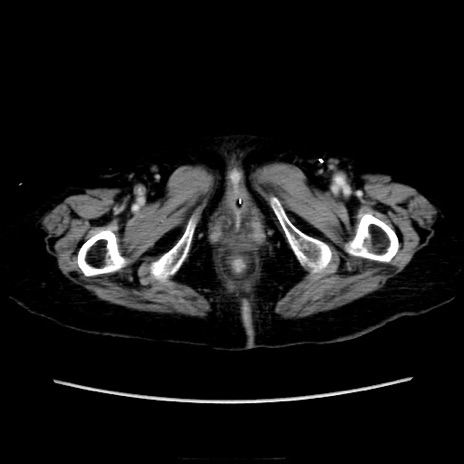

症例40(横断像)

横断像